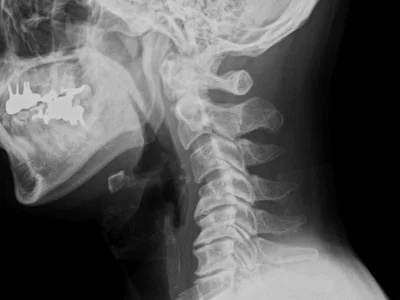

ストレートネック・スマホ首の症例

ストレートネックによる偏頭痛が改善した症例 【吹田市 40代男性】■ 患者の症状長年にわたる偏頭痛と肩こり。1日9時間以上のデスクワークに加え、仕事以外の時間もスマートフォンを見ることが多く、常に頭が…